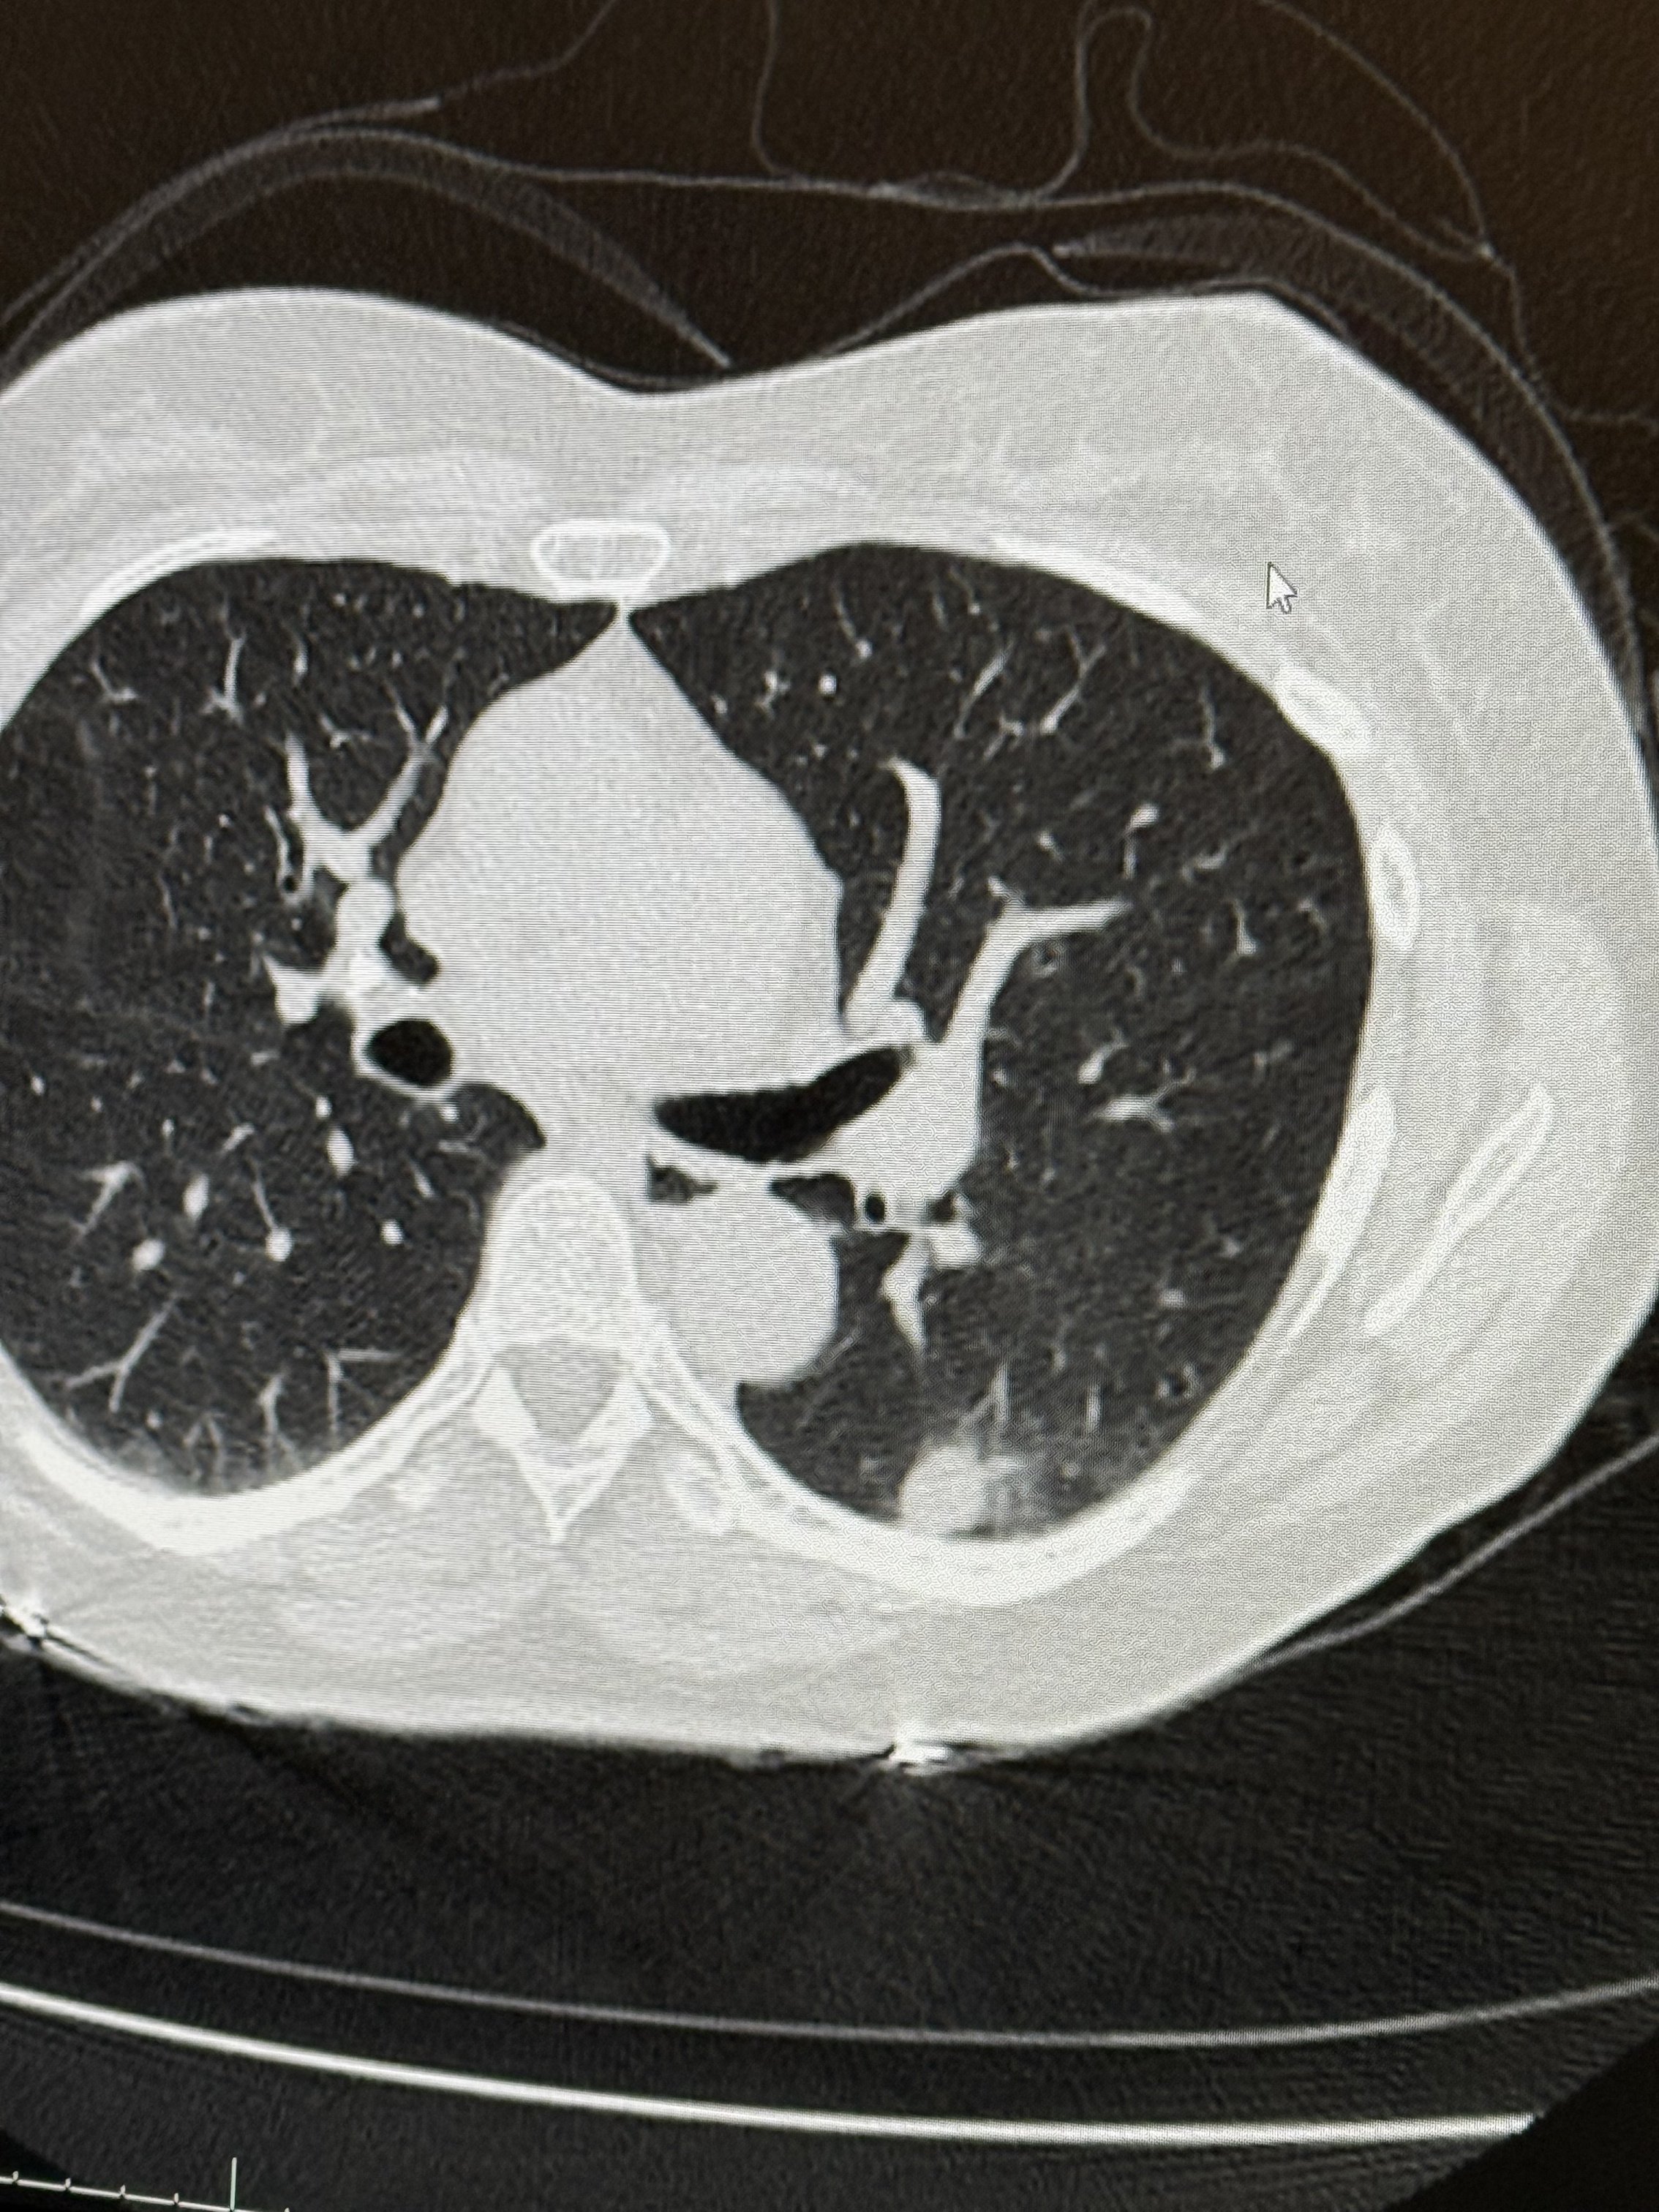

a 12 mm spot was found in my lower left lobe that wasn’t there back in November. CT scan, PET scan, now I have to go back three months which will be April 15 with a new CT scan on March 30.

Not a doctor, but the images you shared look consistent with what you described, a small nodule in the lower left lobe, toward the back, with mild uptake.